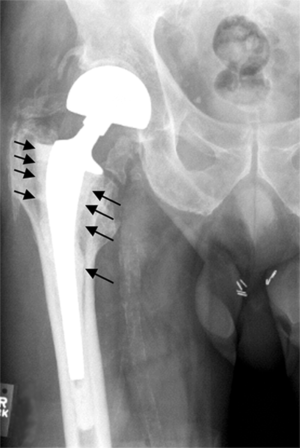

Hip prosthesis displaying aseptic loosening (arrows)